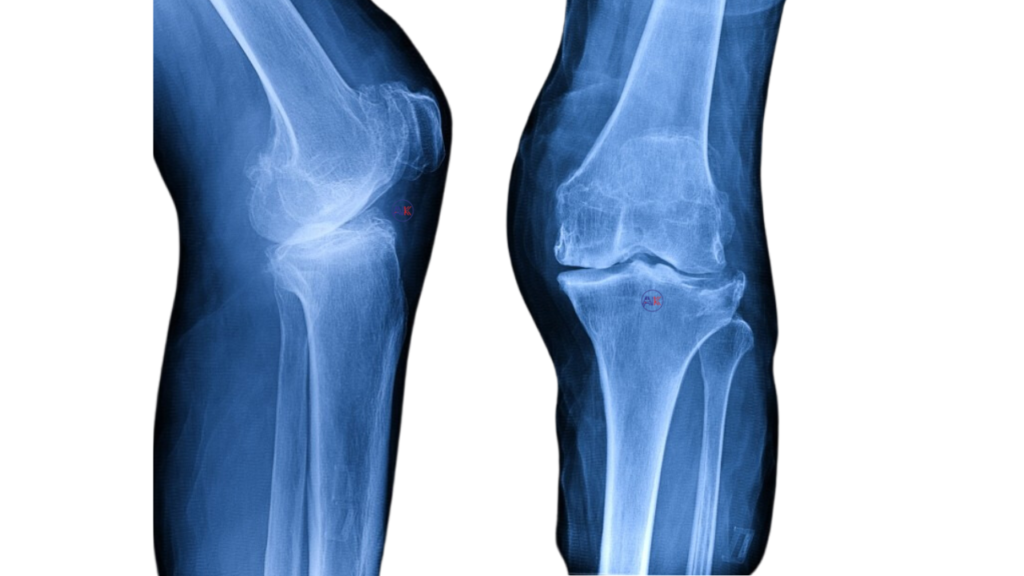

KNEE ARTHRITIS

Knee arthritis includes osteoarthritis and rheumatoid arthritis, involving the gradual degeneration of the knee joint. This leads to pain, stiffness, and decreased mobility.